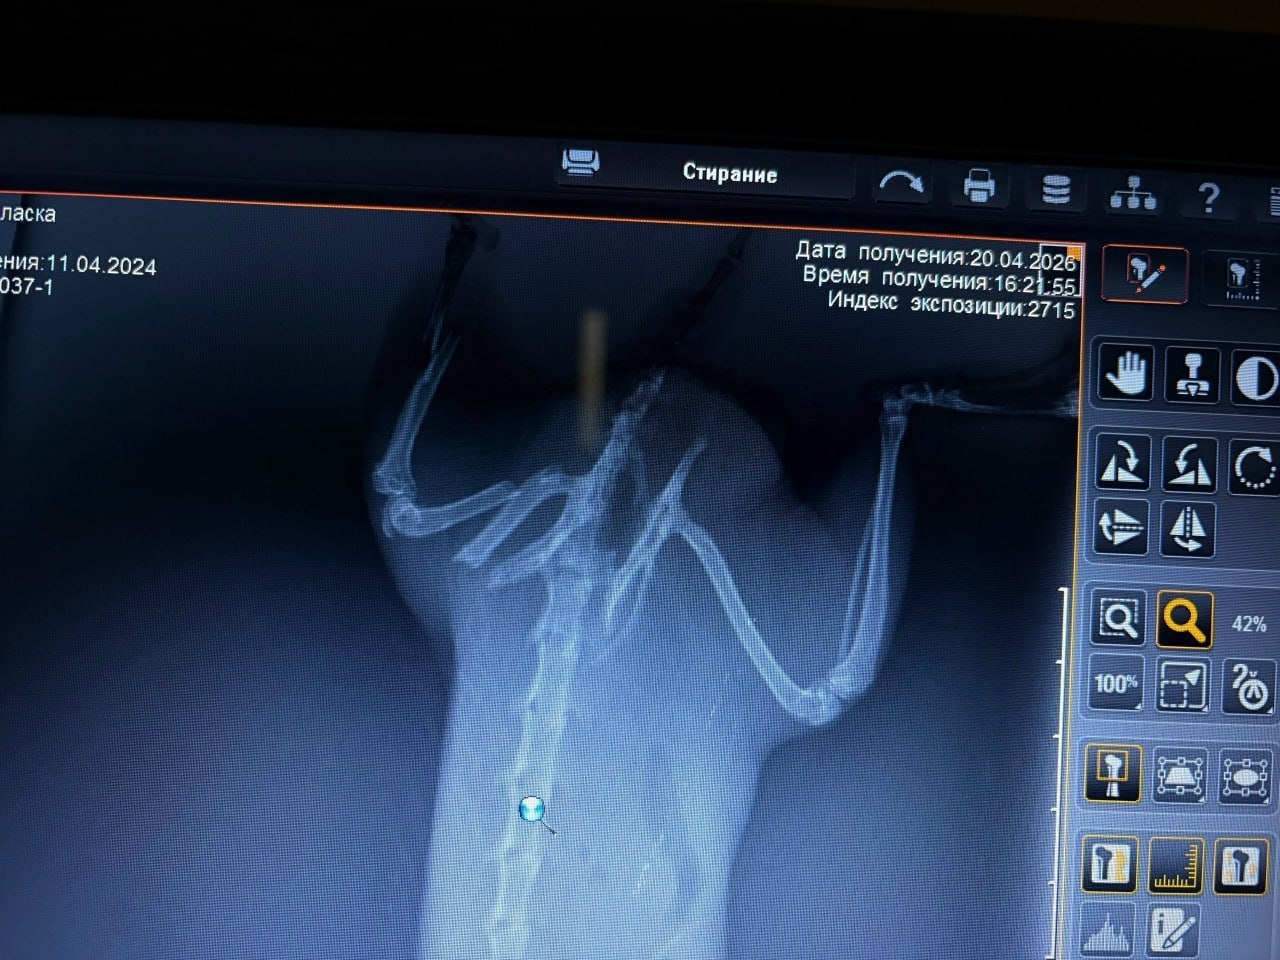

«Сделали рентген, у нее оказался раздроблен таз. Наши врачи-ортопеды отказались оперировать, потому что нет опыта с такими животными. У нас есть женщина, которая дома содержит такую же ласку и состоит в сообществе владельцев этих животных. Она связалась с участниками, скинула результаты обследования. Там ей оплатили билет, договорились с реабилитационным центром на операцию. Сегодня должны были уехать», — рассказала ветеринар журналистам 45. RU.